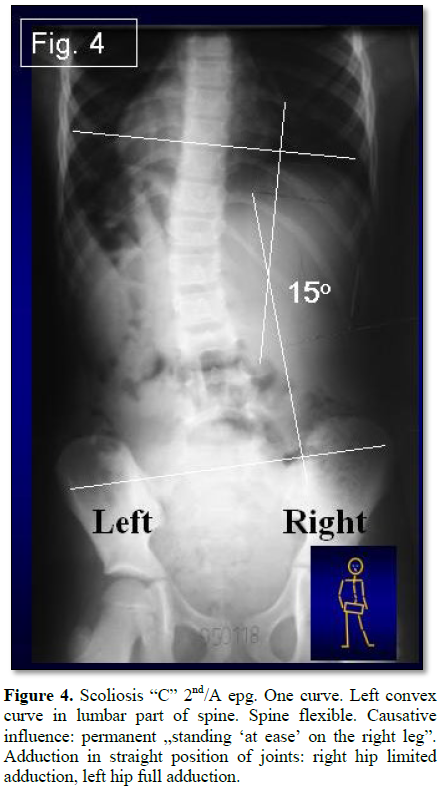

· Scoliosis “C” 2nd/A epg (Figure 4) – one curve – lumbar left convex. Right hip adduction is 15 to 30 degrees. Left hip adduction is 30 to 50 degrees. Spine flexible (1D or 2D); Connection only with standing “at ease” on the right leg.

In the “asymmetrical standing” the loading on the right leg is permanent, lasts longer, and because of this it leads to the development of curves. In scoliosis 2nd epg group comes to “C” deformity in lumbar spine. The clinical symptom in all cases is the lumbar left convex curve.

Scoliosis “C” in 2nd/A and “S” in 2nd/B (Figures 4 and 5) type of deformity in children, there is only a curve in lumbar part and in thoracic part (in “S” scoliosis) to be observed.